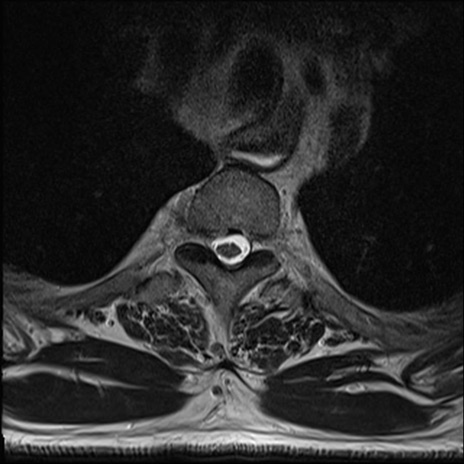

【整形】TIPS症例7 頚椎MRI T2WI(横断像)

頚椎MRI

T2WI(矢状断像)

矢状断像と横断像